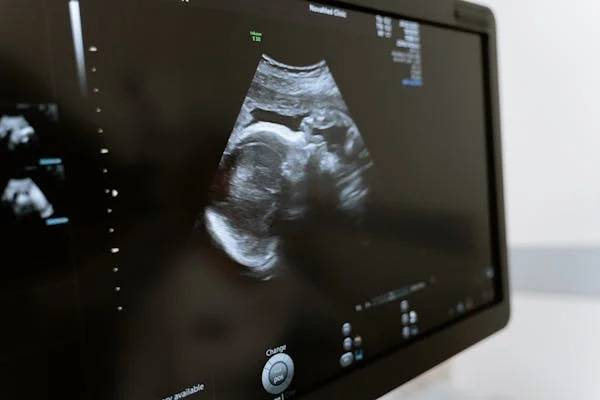

현재는 비침습적 산전 DNA 검사 (Non-Invasive Prenatal Paternity, NIPP) 기술이 발달해

산모의 혈액만으로도 태아의 유전자를 추출해 분석할 수 있게 되었습니다.

NIPP 검사 특징

산모의 혈액 속 ‘태반 유래 DNA’를 통해 태아의 유전정보 확보

임신 7~10주 이후 가능

남성의 DNA 샘플과 비교하여 99.9% 이상의 정확도

안전성 100%, 유산 위험 없음

검사 비용은 약 100~200만 원 선

즉, 바늘로 찌르지 않아도,

병원 가지 않아도,

엄마의 피 한 방울로 아기의 유전자 정보를 분석할 수 있는 시대가 된 것입니다.